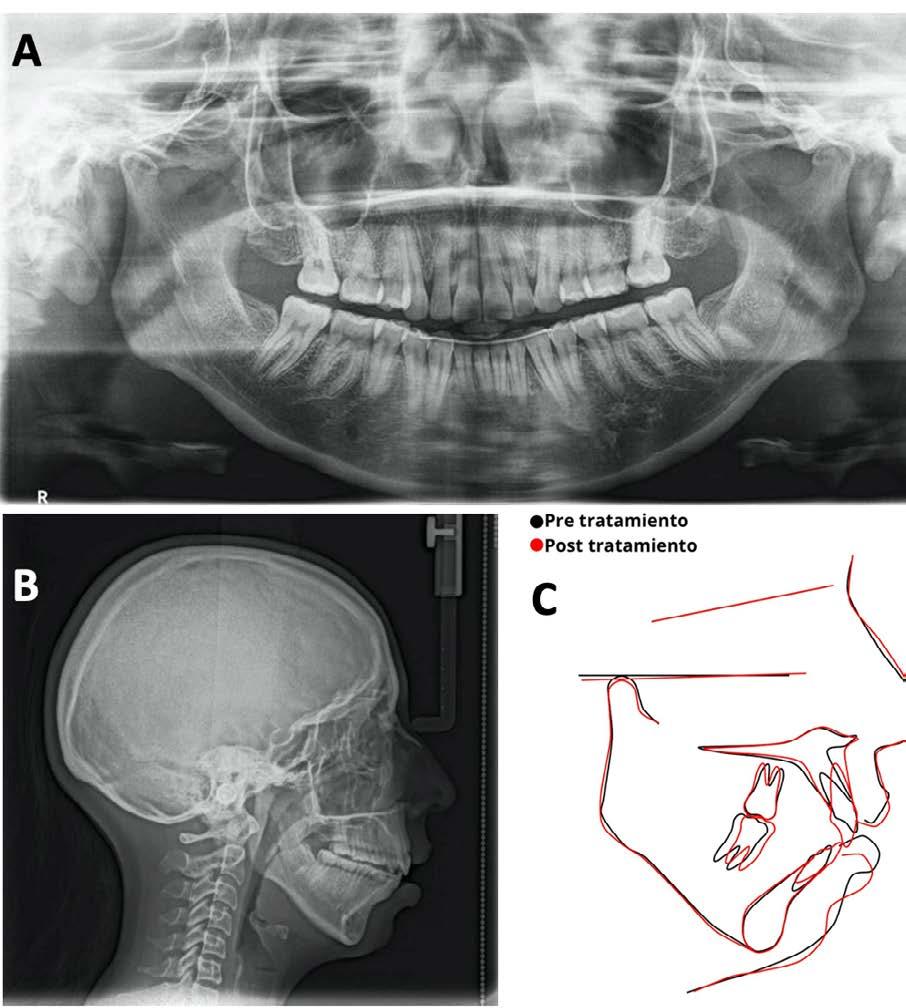

Caso clínico: paciente femenino de 19 años, patrón dolicofacial, perfil convexo, clase II esqueletal debido a una retrusión mandibular, mordida abierta anterior esqueletal, clase II molar, clase canina no establecida por mordida abierta, apiñamiento severo superior e inferior y deglución atípica.

Resultados: obtención de una clase canina I y clase molar II funcional, se corrigieron las sobremordidas horizontal y vertical, y se logró la coincidencia de líneas medias facial y dental. El manejo de la mordida abierta anterior se llevó a cabo por medio de la corrección del hábito de deglución atípica con la ayuda de spikes de resina, elásticos intermaxilares y arcos utility, y se obtuvieron buenos resultados estéticos, dentales y funcionales.